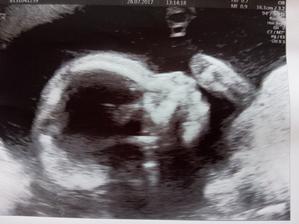

28.7.2017 - druhá genetika screening